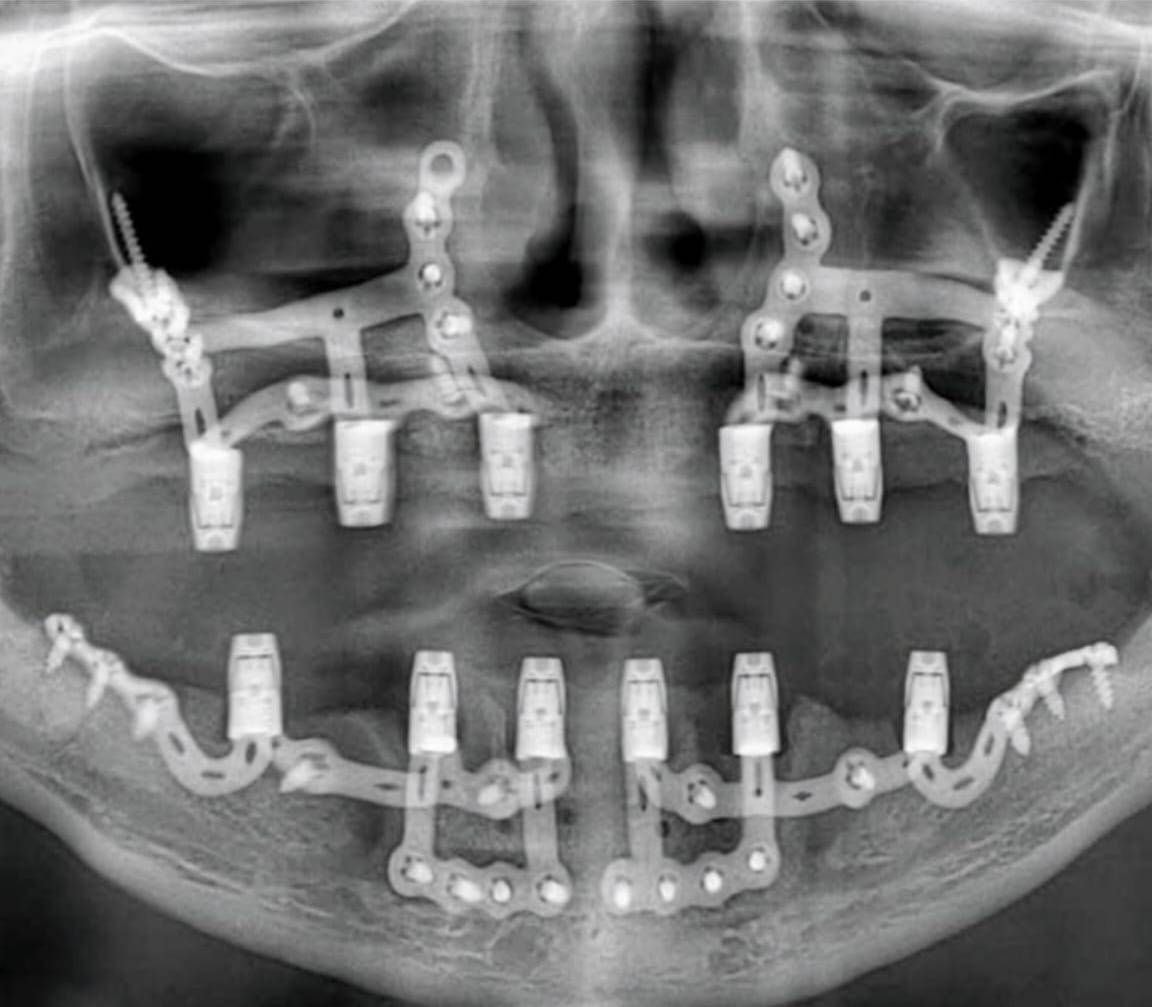

2. Herstellung (Titanstruktur)

Der Entwurf wird im Labor aus Titan mit einem dreidimensionalen Drucker (3D-Drucker) hergestellt.

Diese Struktur wird so vorbereitet, dass sie zu 100% mit der Kieferanatomie des Patienten kompatibel ist.

3. Chirurgische Anwendung

Obwohl die Operation unter lokaler Anästhesie durchgeführt werden kann, wird im Allgemeinen die Vollnarkose häufiger bevorzugt.

Der Chirurg verschafft sich Zugang unter das Zahnfleisch (Gingiva) und fixiert das Implantatskelett auf der Knochenoberfläche.

Die „Abutments“ (Implantataufbauten), an denen die Zahnprothesen befestigt werden, sind meist bereits mit der Implantateinheit verbunden. Der chirurgische Eingriff wird durch das Anbringen von Einheilungskappen (Heilkappen) an diesen Einheiten abgeschlossen.

4. Prothetische Phase

Kurze Zeit nach der Fixierung des Implantatskeletts wird dem Patienten die festsitzende Prothese (Brücke oder Vollbogenrestauration) eingesetzt.

Es ist in der Regel möglich, innerhalb von 2–3 Wochen dauerhaft festsitzende Zähne zu erhalten.